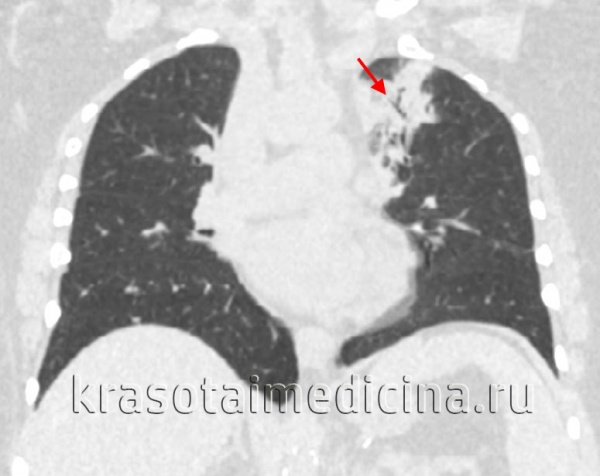

Крайне скудная аускультативная симптоматика сочетается с выраженной дыхательной недостаточностью: одышка, артериальная гипоксемия, респираторный алкалоз. При рентгенологическом исследовании легких обнаруживают облаковидную, туманную, по типу снежной бури, билатеральную инфильтрацию, распространяющуюся от корней легких к периферии. Такие изменения (билатеральные интерстициальные) являются специфичными.

Часто подобные инфильтративные изменения в легких удается выявить только при компьютерной томографии. Возможно атипичное проявление пневмонии (не является редкостью у иммунокомпрометированных больных) в виде локальной, очаговой инфильтрации, присутствия полостей. Появление жидкости в плевральных полостях не специфично для пневмоцистной пневмонии и определяется крайне редко при моноинфекции.

На рентгенограммах и КТ легких в типичных случаях определяется облаковидное понижение прозрачности легочных полей, получившее название «хлопьев снега» или «ватного легкого». Иногда рентгенологические изменения отсутствуют или имеют атипичную картину. С помощью ФВД обнаруживаются признаки дыхательной недостаточности по рестриктивному типу; исследование газового состава крови свидетельствует о гипоксемии.

- Рентгенологические. В начальной стадии пневмоцистной пневмонии на рентгенограммах легких выявляются инфильтраты, похожие на очертания крыльев бабочки. В разгаре инфекции заметны двусторонние симметричные очаги уплотнения, чередующиеся с участками вздутия («ватное» легкое). На КТ грудной клетки обнаруживаются участки инфильтрации по типу «матового стекла».